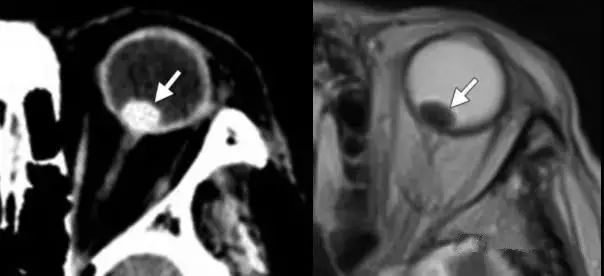

眼球异物

眼内异物可分为有机异物与无机异物 。 最常见的无机异物是金属和玻璃 。 无机异物因化学性质不活泼 , 因而不会引起炎症 。 金属异物在CT上较易诊断 。 玻璃异物因化学成分不同可能密度不同 。

最常见的有机异物是木质异物 。 有机异物可能引起炎症反应 , 甚至严重感染 。 在急性期诊断木质异物可能比较困难 , 因为其影像表现与空气相似 。 鉴别点在于(1)木质异物具有一定的几何形状;(2)木质异物的密度可能随时间变化 , 从亚急性期的等密度到慢性期的高密度;(3)MRI检查见炎性改变也可提示有机异物的诊断 。